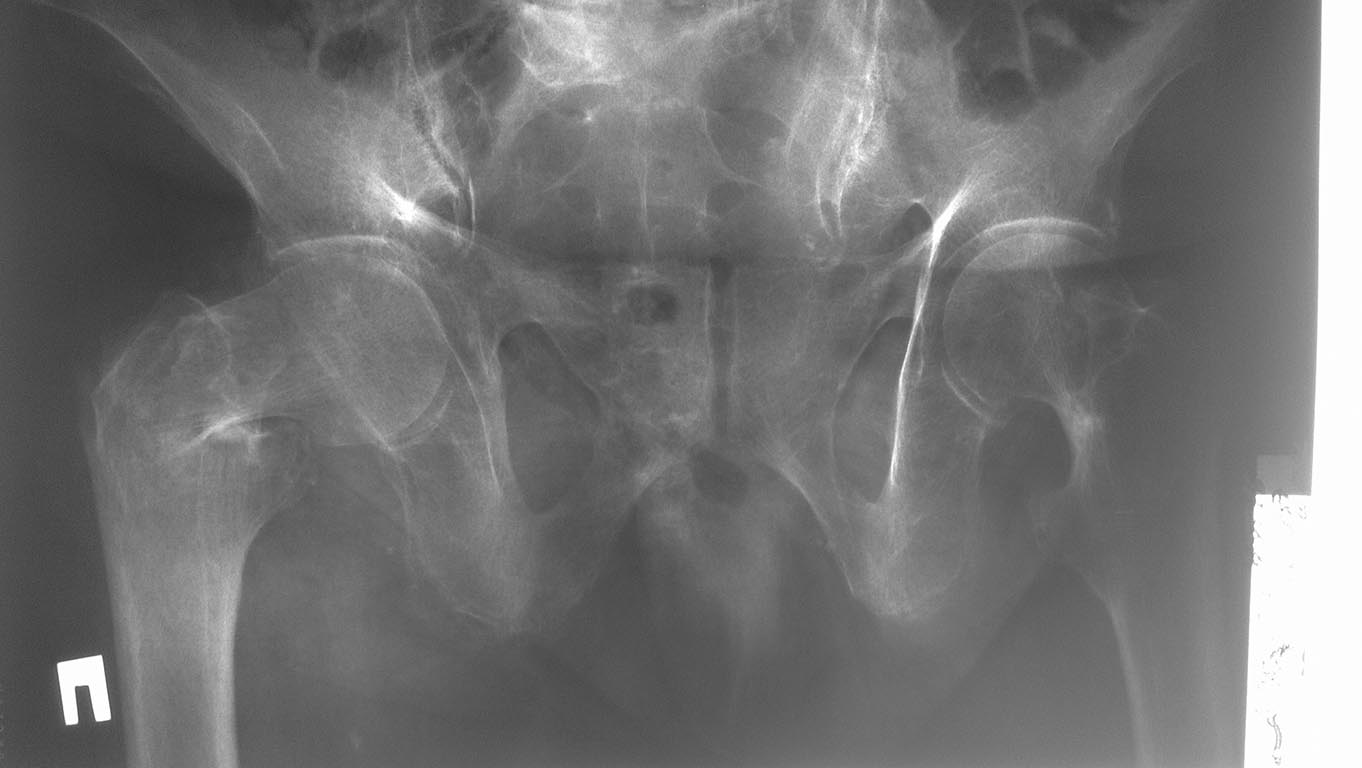

Чрезвертельный или базальная шейка?

Пациентка 1922 г.р., не тучная, без отягощенной соматической патологии,

бытовая травма. Госпитализирована. Не определена тактика лечения ввиду

сложности оценки типа перелома и, соответственно, тактики лечения Если

это чрезвертельный перелом, то вариантов выбора может стать PFN или

угловая пластина Если это базальный (латеральный перелом) шейки - то,

очевидно, стоит рекомендовать эндопротезирование сустава (масса до 100

кг) Помогите оценить ситуацию Спасибо за все ответы